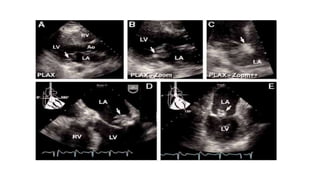

Perivalvular abscess or fistula — When the infective process

spreads beyond the valve leaflets or the cavitary endocardium, it

invades the continuous basal myocardium and tissue of the

fibrous cardiac skeleton.

Early in this process, the organism produces cellulitis, which may

be identified as echodense thickening of perivalvular tissue.

If tissue necrosis and white cell activity continue, the central

portion of this process forms a space-occupying abscess

cavity

Abscess formation is most likely with S. aureus infection.